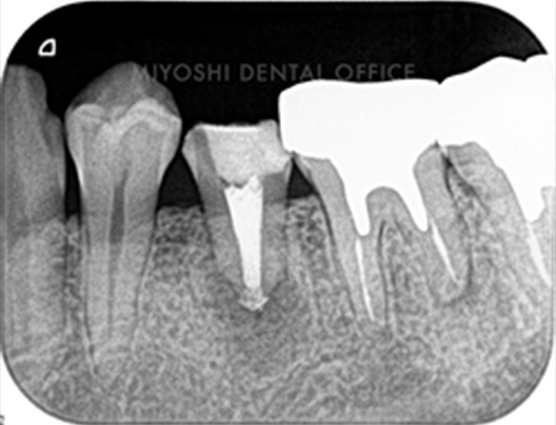

治療前の状態

不十分な薬剤充填によって根管内に隙間ができ、そこから細菌が繁殖して炎症を起こしてしまっています。

当オフィスでの治療例

根管の先まで隙間なく薬剤が充填されており、細菌が繁殖するスペースをなくしています。